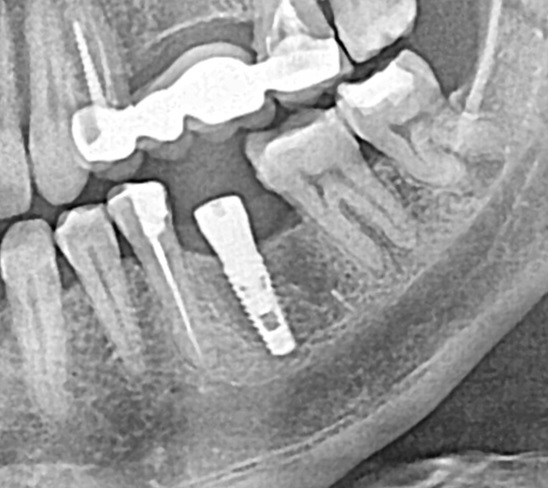

Имплантация в области 26 зуба.

Пациент направлен доктором ортопедом из другой клиники на установку импланта Astra tech в область давно утраченного зуба.

В ходе диагностики мы понимаем: уменьшение длины зубного ряда за счёт мезиального смещения зубов 27 и 28.

Мы можем прогнозировать, что будущий зуб будет меньшего размера чем должен.

Было предложено смещение зубов с помощью ортодонтических микровинтов.

К сожалению, пациент отказался от локальной ортодонтии.

Мне не очень нравятся такие операции, потому что я знаю возможности моей команды и знаю какой возможен результат!

Но лечащий доктор и пациент были за упрощённую схему восстановления...

Клинический случай...

Отсутствие зуба 25

в течение очень длительного времени.

Смещение зуба 26 вперёд - дефицит места.

От ортодонтического лечение отказались.

Этап первый

Установлены ортодонтические винты в область бугра верхней челюсти слева, дана ортодонтическая тяга.

Этап второй

Через 3 месяца мы получили необходимое расстояние и установили имплантант Strauman Blt.

Этап третий

Ещё через 3 месяца мы убедились что имплант полностью интегрирован - пациент передан ортопеду на финальный этап - установку циркониевой коронки и реабилитацию эстетической зоны улыбки.

Доктора:

Ортодонт: Мосунова Ирина Вадимовна.

Хирург-имплантолог: Летягин Тарас Андреевич.